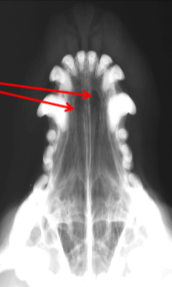

ID Radiographic View

Lateral

ID

Maxilla

Zygomatic Bone

Orbital Margin

Coronoid Process of Mandible